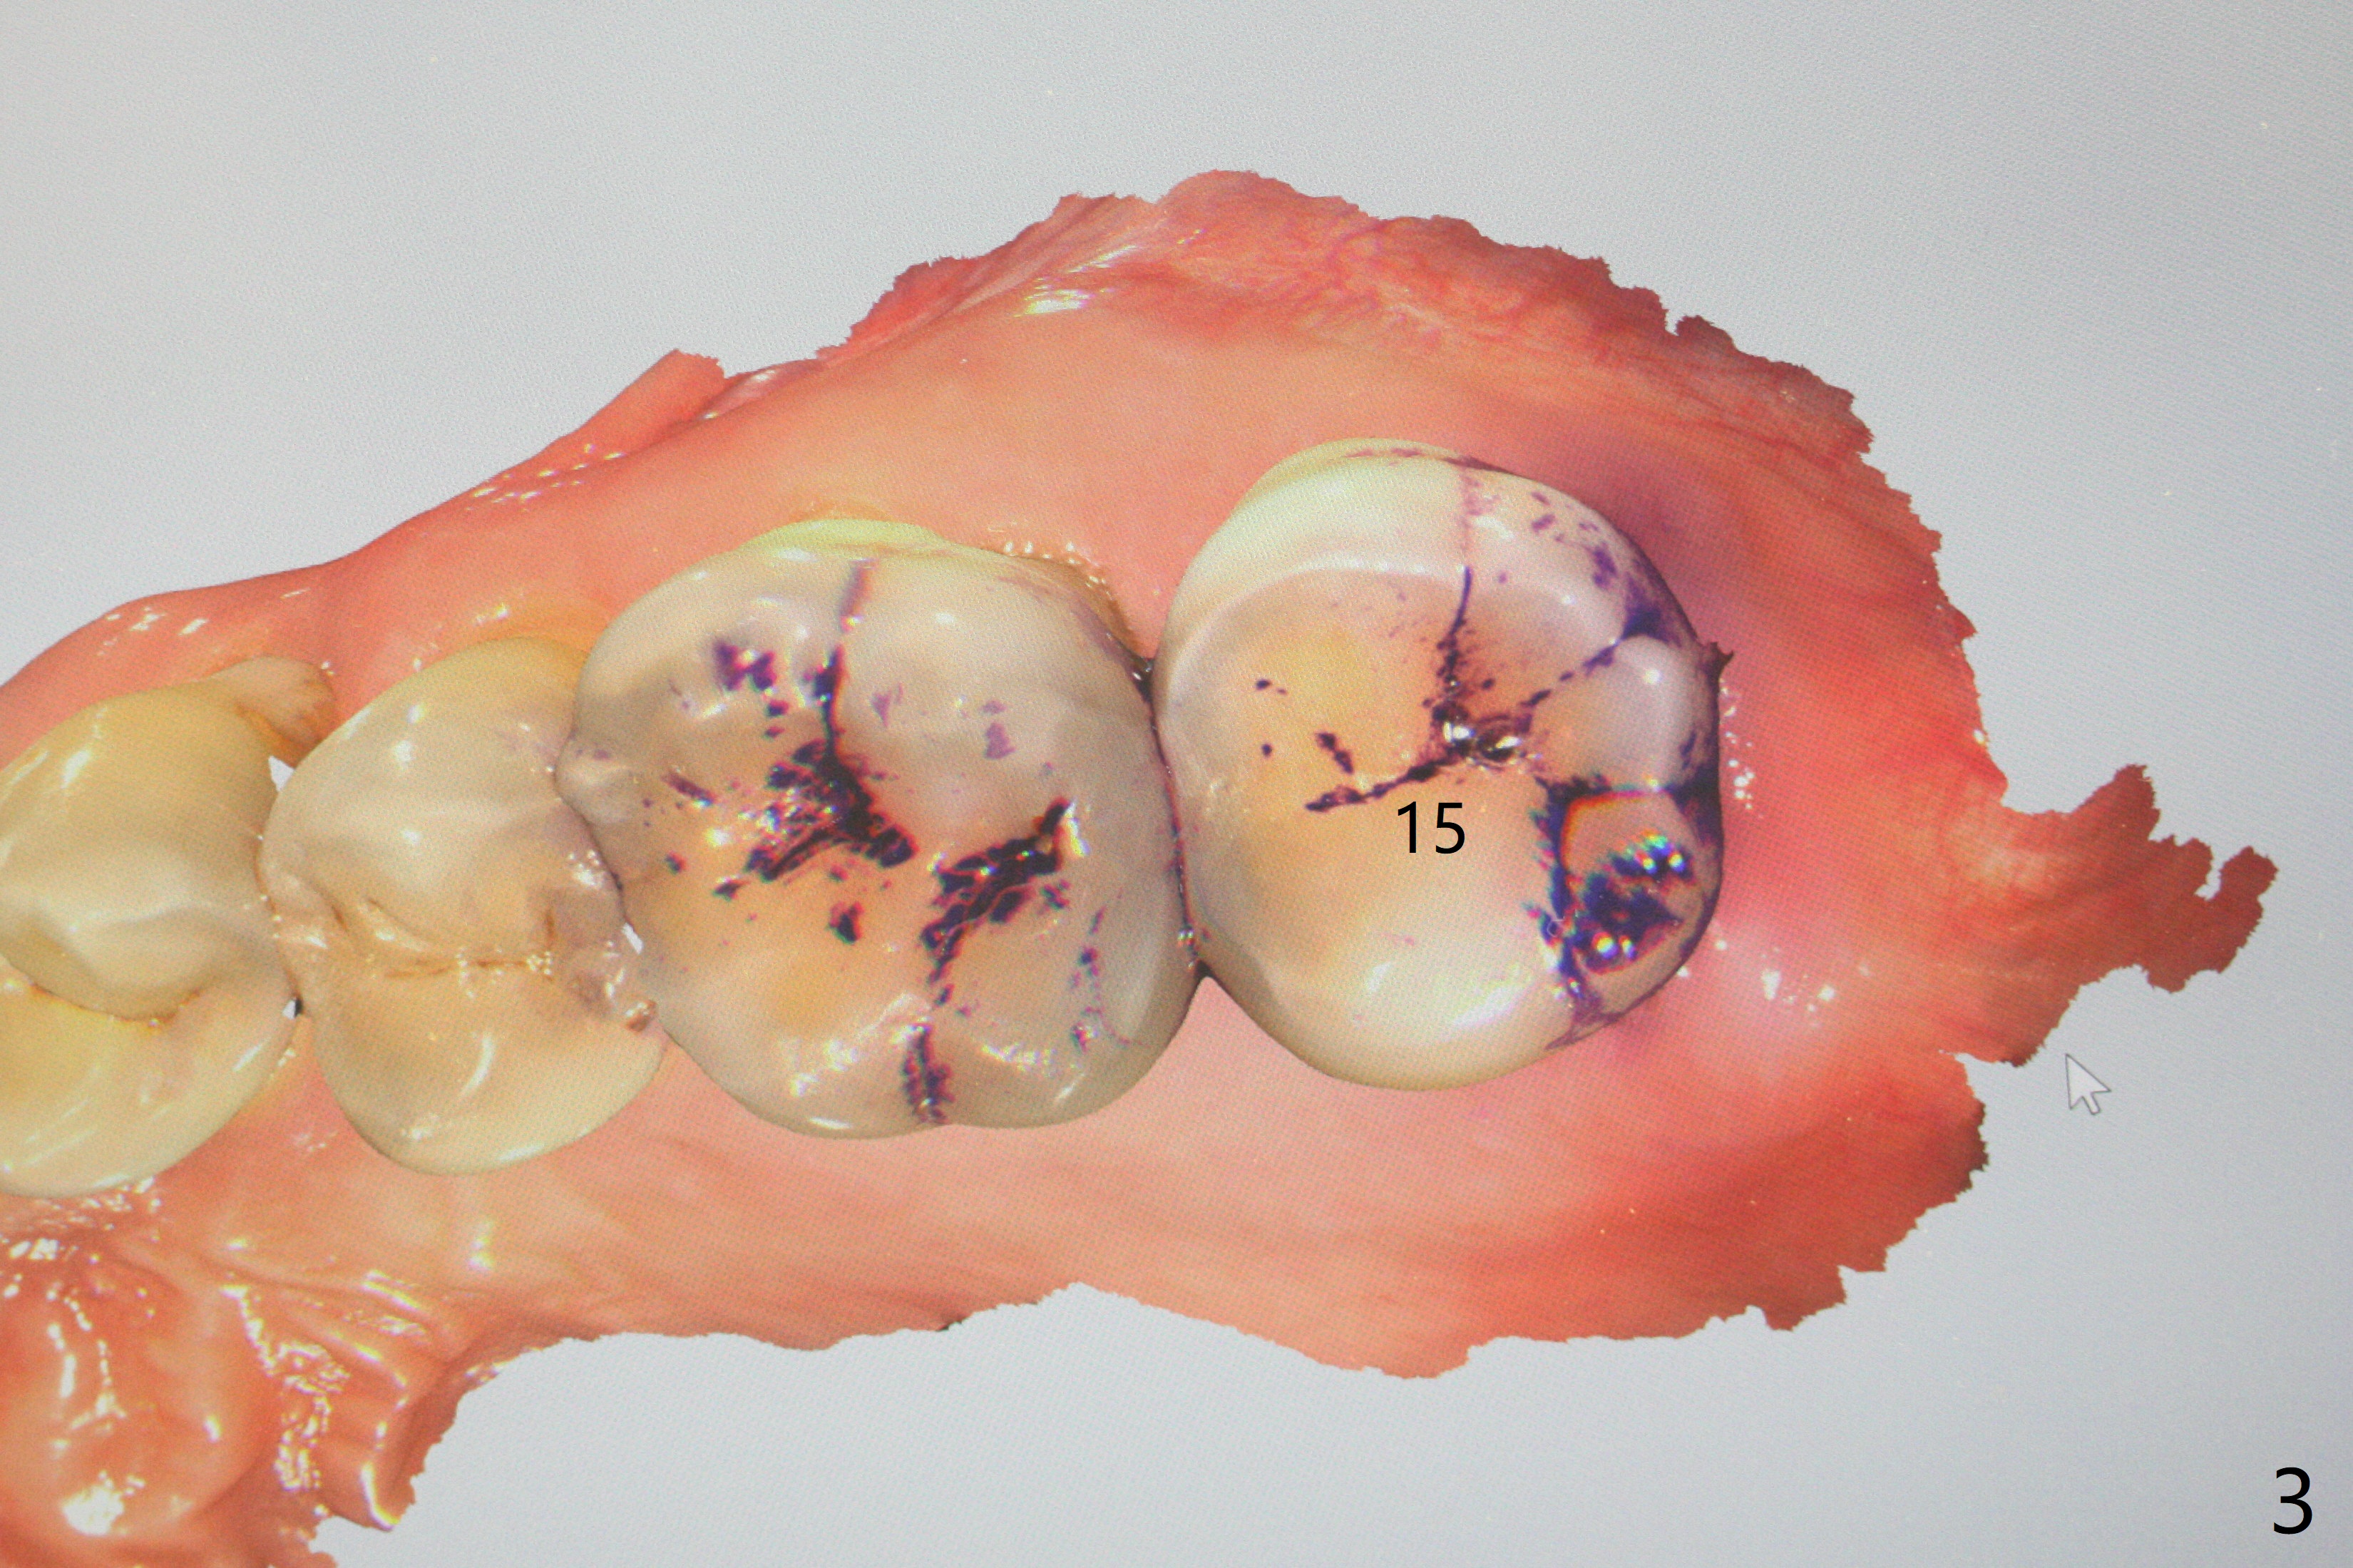

A 62-year-old man with sign of bruxism (#19 porcelain chip (Fig.2), 28 fracture/extraction) complains of severe mastication pain at #15 (Fig.1). More severe pain is elicited when the buccal cusps bite on a bite stick than the palatal one (Fig.3 with suspicious crazing lines). CT shows bone loss around the palatal root (Fig.4 P). A 5x11.5 mm implant will be placed immediately (Fig.5). The bone at #28 is able to hold a 3.5x13 mm implant (Fig.6). It is extremely difficult to take photos for 2nd molar crack line with a regular camera (Fig.3). The Shining Oral Scanner acts additionally as an intraoral camera. As a busy clinician, I do not have time to take photos for #19 porcelain chip. My assistants take over the task. After work, I am able to have bumper harvest. With the information just mentioned, I will be in a better position to present a more comprehensive treatment plan to the patient when treatment at #15 is finished: remove #18-20 bridge, place an implant at #19 and fabricate new crowns at #18 and 20.